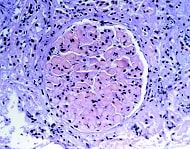

抗リン脂質抗体

母親が抗リン脂質抗体をもっていると、胎盤の血管に血栓性の梗塞が生じたり、胎児の成長が遅れたり、死亡したり、流産を起こすことがあります。これは、SLEの活動性とは関連しません。

抗リン脂質抗体は血栓を誘発し、血管を詰まらせる作用があるのです。治療は、基本的には少量のアスピリン、プレドニン、ヘパリンを組み合わせて行います(毎日皮下注射、あるいは入院が必要)。